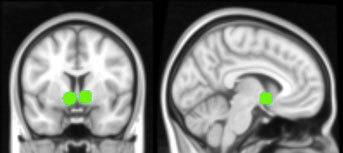

A region that was especially active is a part of the striatum called the nucleus accumbens, which is part of the brain’s reward circuitry, she said. This reward circuitry is thought to be particularly sensitive during adolescence. When the teenagers saw their photos with a large number of likes, the researchers also observed activation in regions that are known as the social brain and regions linked to visual attention.

Credit: Lauren Sherman/UCLA